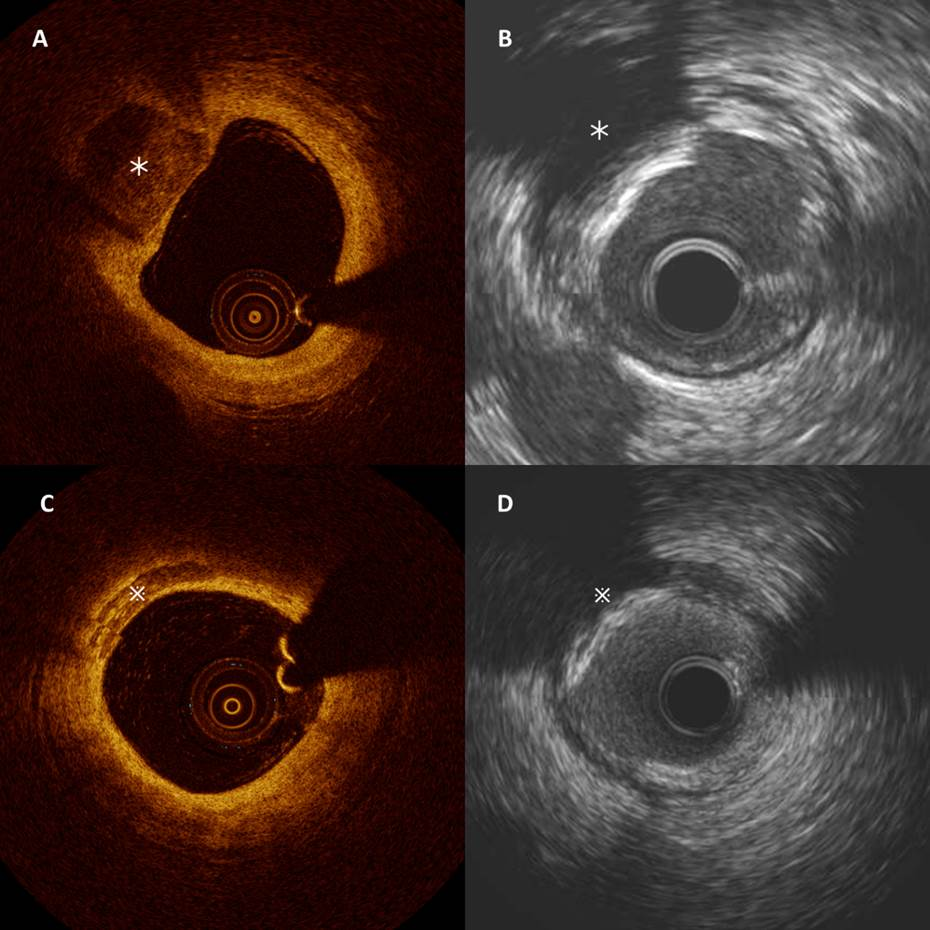

In patients with stent failure, IVUS or OCT is reasonable to determine the mechanism of stent failure (Class IIa).

• "Assessment  of  the  cause  of  stent  thrombosis  with  intracoronary  imaging  is  important to guide subsequent treatment. Similarly, advanced  imaging  techniques  have  an  important  role in detecting underlying mechanical and pathophysiological  factors  that  contribute  to  in-stent  restenosis  (ISR),  such  as  neointimal  hyperplasia,  stent  underexpansion,  and  fractures."

• "Registry and case series data  have  demonstrated  that  IVUS  and  OCT  can  be  useful  for  evaluating  the  mechanisms  of  stent  restenosis  and  stent  thrombosis."

• "OCT  is  better   at   differentiating   between   stent-related   mechanisms,  whereas  IVUS  is  preferred  for  in-depth vessel wall characterization."

Stent Assessment

https://www.acc.org/latest-in-cardiology/articles/2016/06/13/10/01/intravascular-oct-in-pci